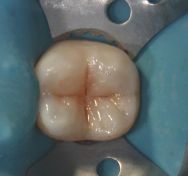

La paziente mostrava clinicamente un solco occlusale nel quale si impegnava appena lo specillo. Si intuiva la presenza di una piccola carie. In realtà, una volta aperta la cavità, la carie mostrava di aver sottominato una disreta quantità di smalto occlusale. Una volta ripulità è stat eseguita un restauro in composito.

Otturazione occlusale di secondo molare inferiore.

Il caso mostra la cura in composito di una carie occlusale (I classe di Black) di un molare inferiore.